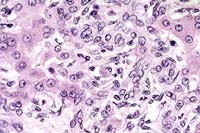

Case 22-1. Liver. Proliferating lumenless bile ductule epithelium and fibroblasts in the portal area are infiltrating the limiting plate of the lobules, with a few neutrophils. An individual ductule cell has eccentric cytoplasm containing a microsporidial cyst with 0.5-1.0µ spores (Enterocytozoon bieneusi). 40X

AFIP Diagnosis: Liver: Hepatitis, portal and periportal, bridging, lymphoplasmacytic and neutrophilic, chronic, with biliary hyperplasia, multifocal periportal hepatocellular necrosis, and rare extruded individual biliary epithelial cells containing microsporidial organisms, Rhesus monkey (Macaca mulatta), primate.

Contributor's Diagnosis and Comments: Liver: Nonsuppurative cholangiohepatitis with marked proliferation of bile ductules, bridging portal fibrosis and extrusion of individual biliary epithelial cells containing microsporidial organisms.

Infection with E. bieneusi has been diagnosed in three species of macaques (Macaca mulatta, M. cyclopis and M. nemestrina) and the organism may be identified in both immunocompetent and immunodeficient individuals. This organism is virtually indistinguishable at the morphologic and genetic level from that identified in human AIDS patients. In immunodeficient animals, the organism is most commonly found in the gall bladder and common bile duct and less frequently in the small intestine and liver. The characteristic findings in the gall bladder and common bile duct are a nonsuppurative and proliferative cholecystitis and choledochitis. As seen in this case, extrusion of individual biliary epithelial cells is often evident. These cells contain mature spores which are visible as 1.0-1.5 um diameter negative images or lightly basophilic bodies on routine H&E stained sections. In our colony, the triad of bridging portal fibrosis, nodular lymphocytic infiltrates and marked bile duct and ductular hyperplasia within the hepatic parenchyma has been found exclusively in association with E. bieneusi infection. In these cases, the organism is found most commonly in intralobular hepatic ducts and less frequently within proliferating bile ductules.